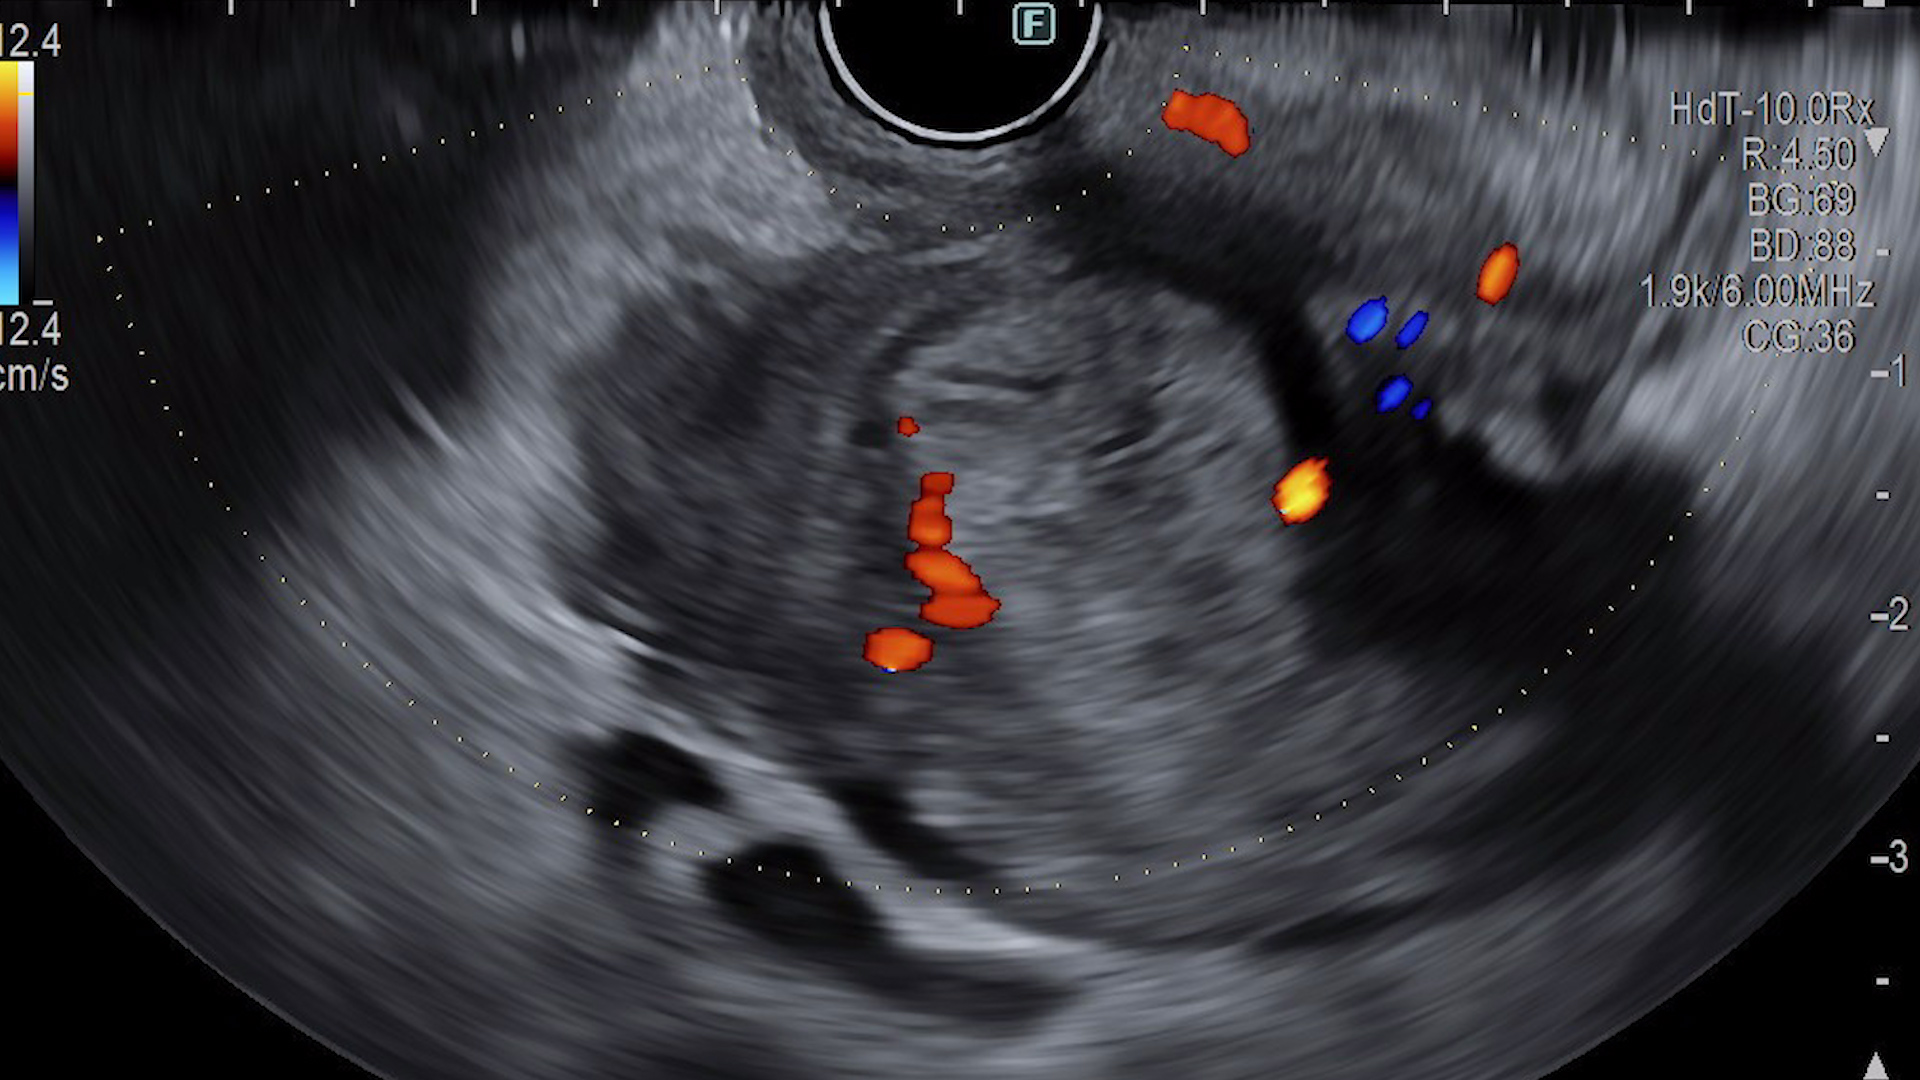

EUS examination showed a large collection with debris inside, non-enhanced during contrast-enhanced harmonic imaging. Drainage was performed with a lumen apposing metal stent (LAMS) of 15 mm diameter (HotAxios, Boston Scientific, USA), without complications. Two weeks later the patient was readmitted for pain and fever. An upper endoscopy was performed showing the stent, which was clogged with blood clots. Consequently, we decided to remove the LAMS and replace it with two double-pigtail plastic stents. The stent exchange underwent without any complications, the patient had afterwards a favourable clinical and biological evolution.